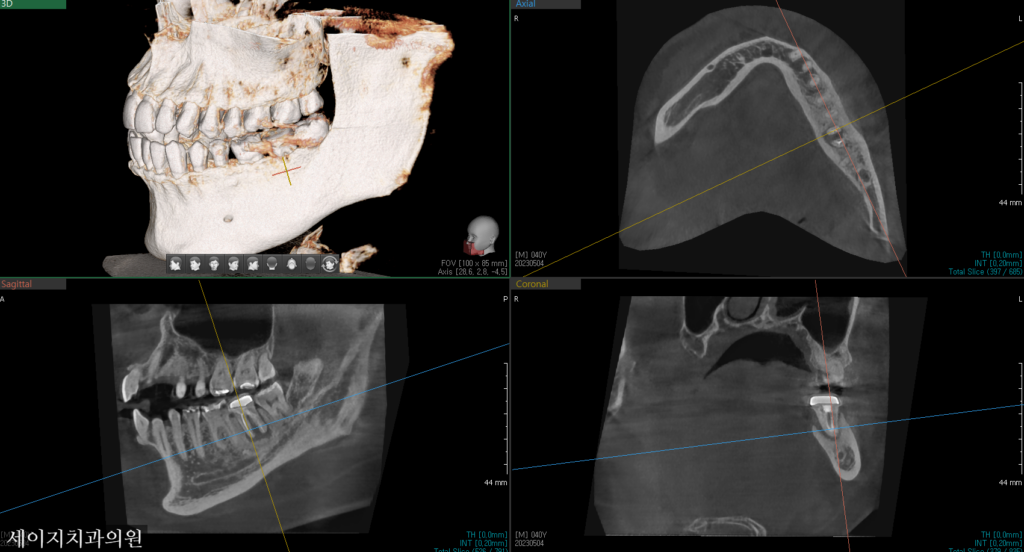

가장 최적의 위치에 모의로 임플란트 수술을 진행해 보았습니다. 이상적인 위치 관계를 설정한 후, 하치조 신경관과의 거리를 정확히 계산한 후 임플란트의 직경, 길이 등을 설정하였습니다. 향후 보철적인 관계를 위하여 대합되는 상악의 어금니와의 관계를 고려하였습니다.

CT를 이용한 기존 모의 수술과 비슷한 결과값을 얻었으며 수술당시 광범위한 뼈이식을 통해 골조직을 재건해드렸습니다.

뼈이식은 이식재의 선택부터, 연조직의 핸들링까지 숙련된 치과의사에게 시술받아야 합니다. 감염으로부터 보호하기 위해 적절한 조치가 이루어져야 하며, 환자의 통증조절을 위해서도 여러가지 임상적인 노하우가 필요합니다.